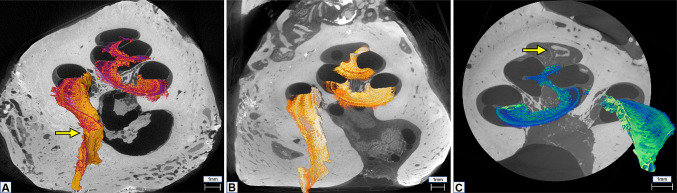

Fig. 2.

A MicroCT of cochlea 1 at 13-µm voxel size resolution. Yellow arrow points to a tear on the OSL. B MicroCT of cochlea 2 at 14-µm voxel size resolution. C MicroCT at 4.5-µm voxel size resolution. Yellow arrow shows inner cochlear calcifications and fibrotic tissue formation